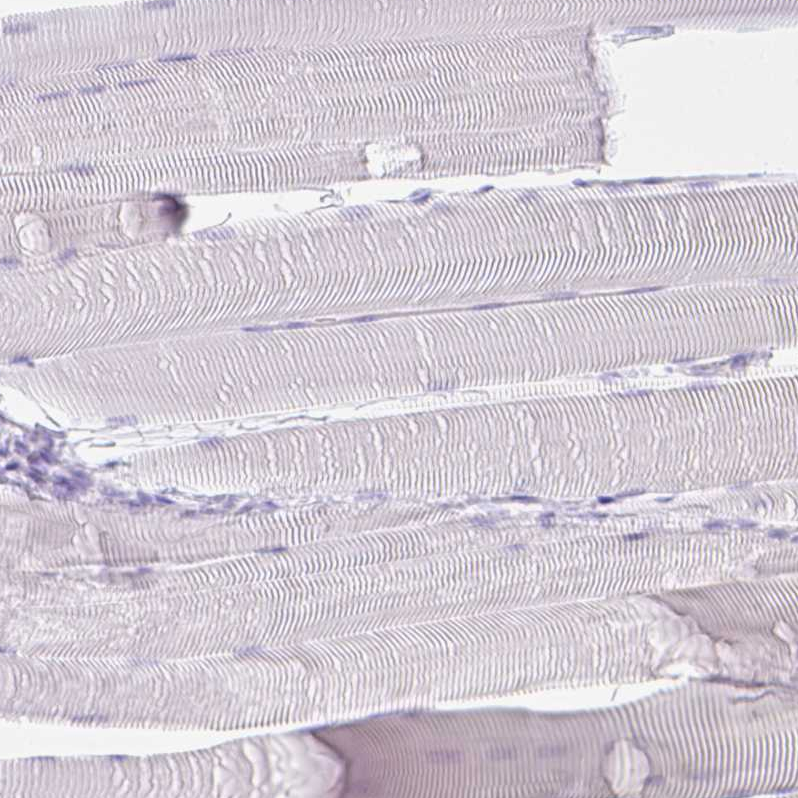

Immunohistochemistry analysis in human colon and cerebral cortex tissues using HPA031186 antibody. Corresponding LGALS4 RNA-seq data are presented for the same tissues.